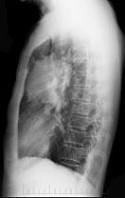

问题 女性,51岁,胸痛数月,痰血两天,X线检查见图,最可能的诊断是 ( )

选项 A、左肺转移瘤 B、支气管扩张 C、左侧炎性假瘤 D、左侧纵隔肿瘤 E、左肺癌

答案 E